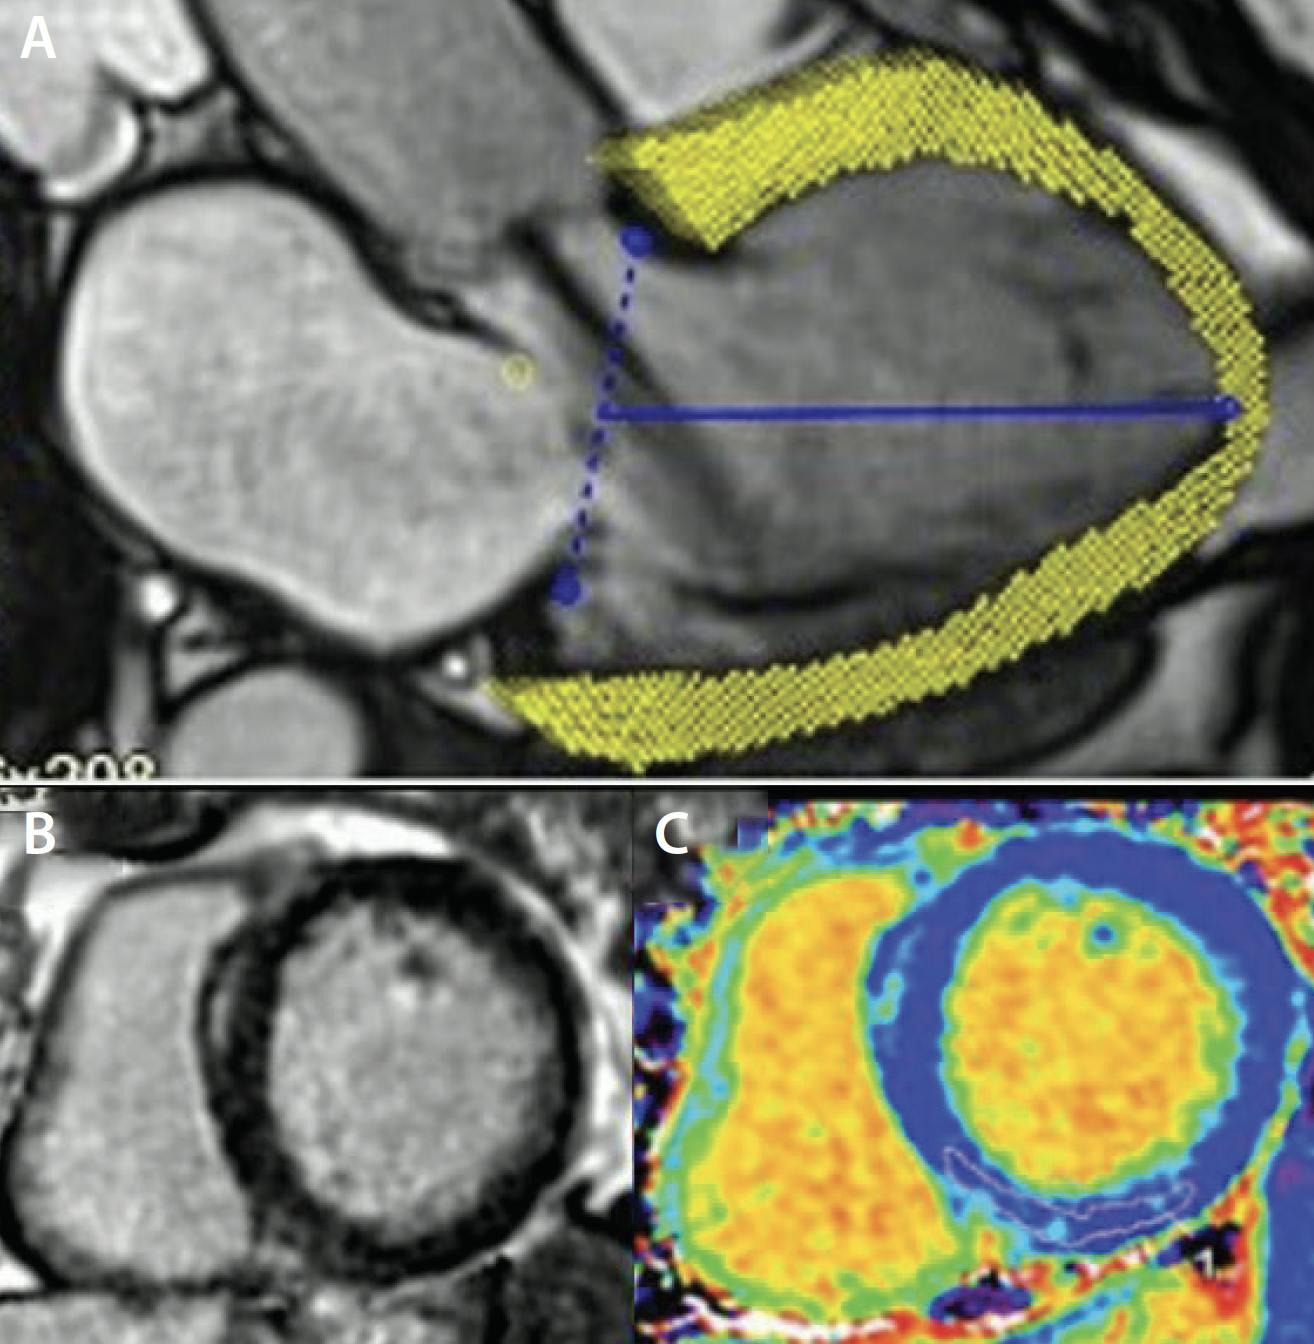

Basal linear LV dimensions are misleading, particularly because the greatest LV remodeling typically occurs at the midcavity and varies according to patient sex. LV end-systolic volume index (LVESVi) ≥ 45 mL/m2 was independently associated with increased mortality risk in asymptomatic patients with moderately severe to severe AR.8 However, we must pay careful attention to the assessment of LV volumes in patients with poor imaging quality and avoidance of image foreshortening, which reduces reproducibility of this method. Although 3D echocardiography allows for more accurate measurement of LV volumes and LVEF than 2D echocardiography, it still requires good acoustic windows. Furthermore, its incremental role beyond 2D volumes in patients with AR remains to be determined (Figure 2A).

Figure 2. The quantification of LV remodeling by 3D echocardiography (A), cardiac MR (B), and CT (C). LA, left atrium; LV, left ventricle. Reprinted from J Am Soc Echocardiogr, Vol 31, Acquatella H, Asch FM, Barbosa MM, et al, Recommendations for multimodality cardiac imaging in patients with chagas disease: a report from the American Society of Echocardiography in collaboration with the InterAmerican Association of Echocardiography (ECOSIAC) and the cardiovascular imaging department of the Brazilian Society of Cardiology (DIC-SBC), Pages 3-25, Copyright 2018, with permission from Elsevier.

CMR: The Gold Standard Assessment

CMR provides high reproducibility and accuracy for quantification of LV function and volumes (Figure 2B).9 Hashimoto et al suggested that LVESVi > 45 mL/m2 on CMR was associated with increased risk of cardiac events in asymptomatic patients with chronic moderate or severe AR.10 This threshold is similar to the 45 mL/m2 threshold from previous echocardiographic literature.8

Functional CTA: An Alternative Imaging Modality for LV Remodeling and Function

Functional CTA is also useful for the assessment of LV function and LV volume (Figure 2C), offering high accuracy that is comparable to CMR.11 However, the accuracy and quality of these measurements can be affected by the patient’s heart rate, presence of arrhythmia such as atrial fibrillation, and the CT scanner system used for acquisition. Dual-source systems have the best-in-class temporal resolution, allowing for absolute millisecond reconstructions. The technology for volumetric scanners covering the entire heart within one cardiac cycle offers better temporal resolution.